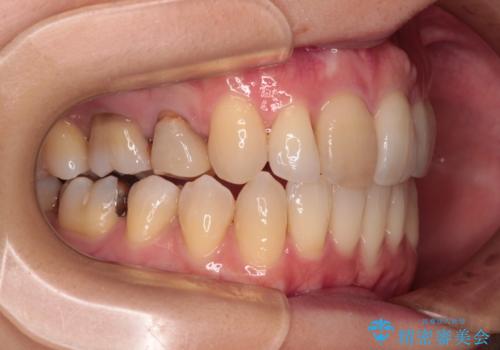

- 口を閉じたときに飛び出してしまう上顎前歯を気にして来院された患者様です。

上下の咬み合わせは上顎歯列全体が歯1本分前にずれている状態であり、さらに上顎歯列はV字型に尖っていたため、上下前歯は全く接触していない状態でした。

上顎左右第一小臼歯を抜去して、ワイヤー装置にて口元の突出感を改善するよう矯正治療を行うこととしました。